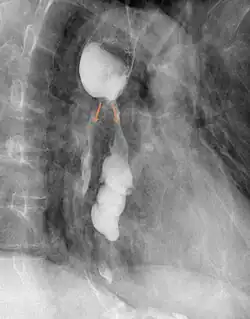

Der Großteil der Fälle kann durch eine Röntgenaufnahme des Thorax erkannt werden. Luft im Mediastinum (Mittelfell) mit Verbreiterung desselben, Hautemphysem, sowie Flüssigkeitsspiegel im Mediastinum oder ein Sero-/Pneumothorax bei Rupturen im unteren Ösophagusdrittel sind Hinweise auf eine Perforation. Auch ein exsudatbedingter Pleuraerguss kann im Rahmen einer Ösophagusperforation entstehen.[1] Weiterführende Verfahren sind Kontrastmittelaufnahmen oder eine Darstellung in der Computertomografie. Endoskopische Untersuchungen können hilfreich sein, unter Umständen die Perforationsstelle aber übersehen.